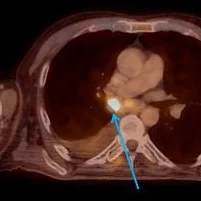

Case 2: Filling defect with clear iodine uptake (red arrow).

Case 2: Intense uptake on PET scan (blue arrow)